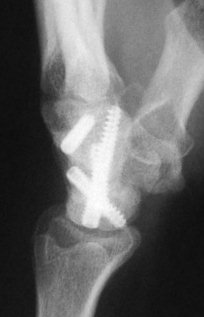

Clinically and by bone scan, this patient sustained a scaphoid fracture, but obviously had a preexisting distal pole cyst.

Intraoperatively, the distal pole cyst was eggshell thin with comminution into the ST joint. Stable fixation was not possible, even with a radial

styloid bone graft, and the distal pole was excised. Postoperatively, carpal instability was present.